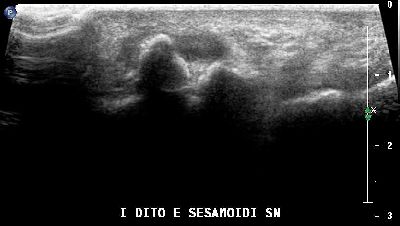

Sesamoide accessorio primo dito interfalangeo (img. 01) Sesamoide accessorio primo dito interfalangeo (img. 01)